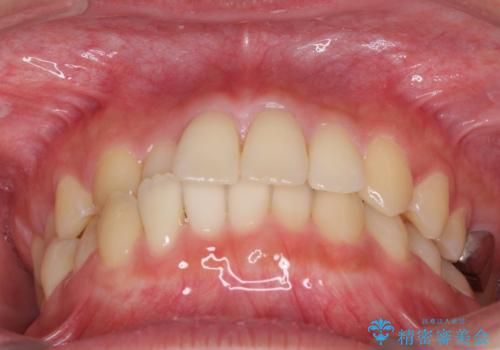

- 前歯のクロスバイトを気にして来院され患者様です。

定期的に日本には帰国するものの、日ごろは海外でお仕事をされているとのことで、インビザラインによる治療を希望されました。

トラブルが起こった時に対応ができない、来院を帰国のタイミングに合わせなければならないため治療が長期化するなど困難はありますが、ワイヤー矯正と比べると治療を進めやすいといったメリットがあるので、インビザラインにて矯正治療を行うこととしました。